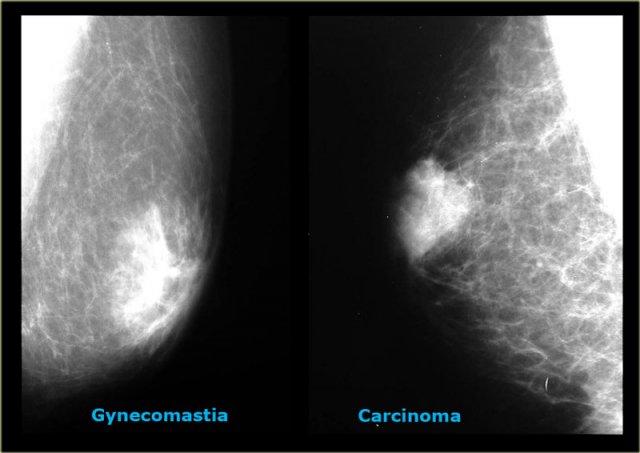

Bên trái là hai trường hợp minh họa cho thấy việc phân biệt vú nam to với ung thư biểu mô trên nhũ ảnh có thể rất khó khăn.

Ung thư biểu mô ở bên phải có bờ được bao bọc rõ hơn một chút so với vú nam to ở bên phải.

Trong chưa đến 10% các trường hợp, cần sinh thiết để phân biệt hai thực thể này.